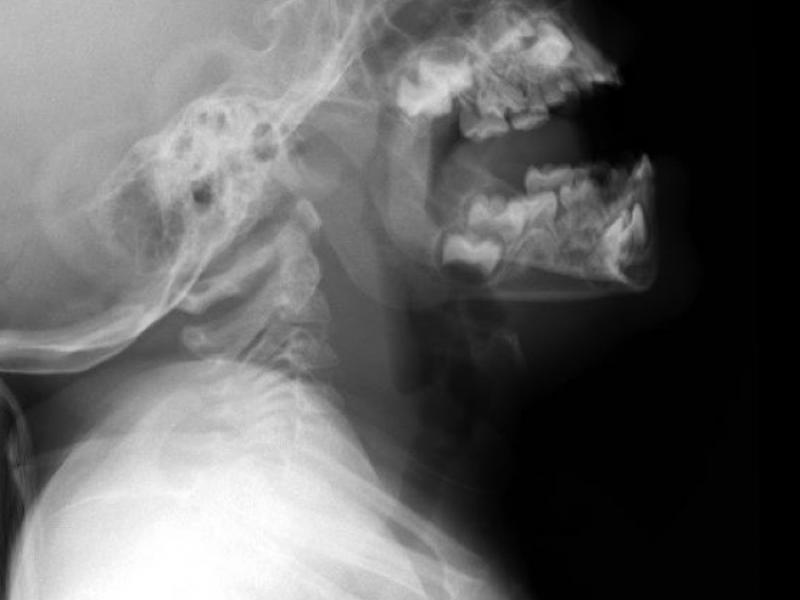

What's the diagnosis? By Dr. Katie Selman